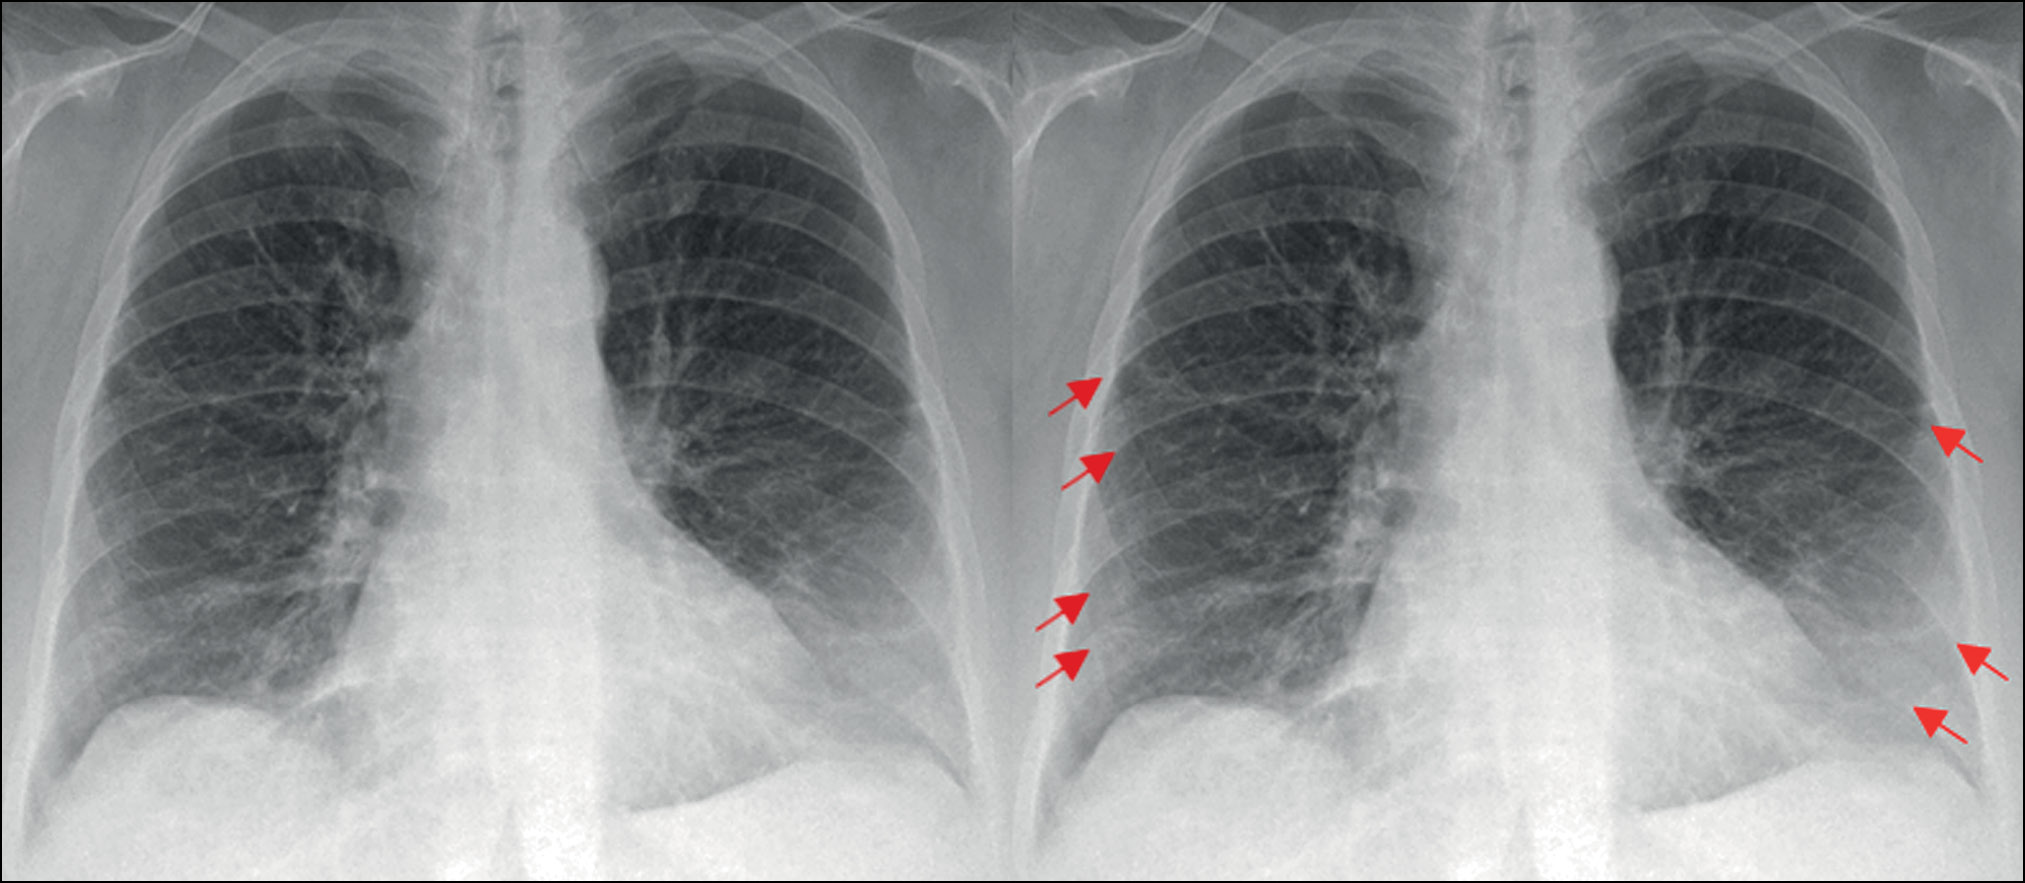

В другом случае ИИ-сервис, опять же по причине невозможности обработки боковой проекции, не определил фиброзные изменения (рис. 9).

Рис. 9. На боковой проекции определяются фиброзные изменения в заднем косто-диафрагмальном синусе справа, которые не видны на прямой проекции (сервис искусственного интеллекта их не определил ввиду обработки только прямой проекции). Аналогично данным изменениям сервис может «пропустить» минимальный плевральный выпот.